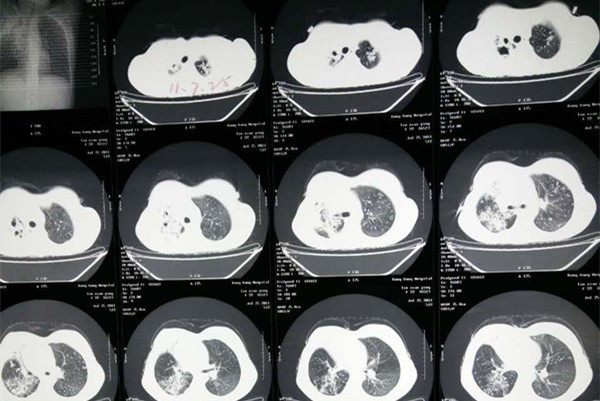

当采用一线抗结核药物治疗肺结核后,痰菌持续不阴转,临床表现没有改善,甚至症状加重,那就需要考虑是否已经发生了耐药,诊断耐药肺结核,除了常规的痰涂片、胸部影像学检查、痰培养、分子快速诊断外,还要通过传统药物敏感性试验或分子生物学快速检测技术来诊断所感染的结核分枝杆菌是否对某一种或多种抗结核药物耐药,若存在耐药,证明该药物治疗无效。精准的诊断对于后期耐药方案的制定有很大的帮助。那么肺结核耐药怎么治疗呢?